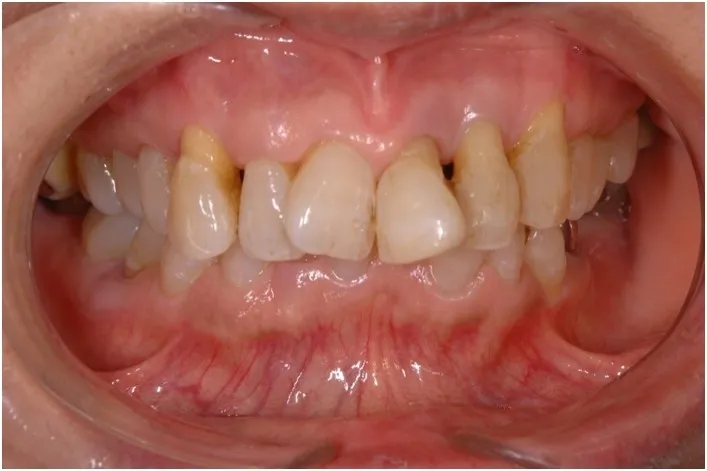

【治療前】

【治療後】